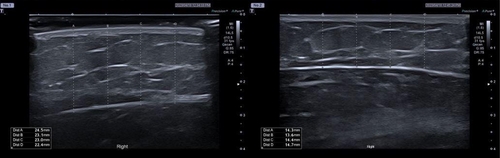

연구에 따르면 ㎖당 5㎎, 2.5㎎ 브이올렛을 팔뚝 부위에 8주에 걸쳐 3차례 시술한 뒤 20주간 관찰한 결과 피하지방 두께가 평균 7.49㎜, 4.68㎜ 각각 줄어든 것으로 나타났다.

상완 팔 둘레 길이도 평균 1.55㎜, 1.1㎜ 감소한 것으로 확인됐다.